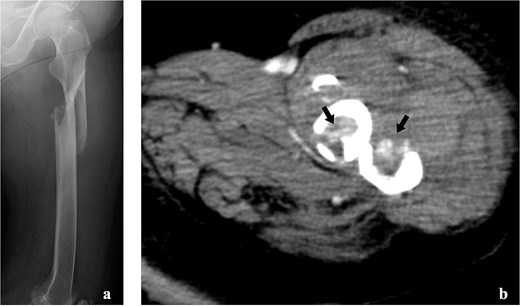

Radiography revealed a femoral shaft fracture (Fig. 1a), and contrast-enhanced computed tomography revealed a blush around the fracture site (Fig. 1b). Electrocardiography indicated sinus rhythm with ST depression in V3–V6. Echocardiography revealed severe anteroseptal hypokinesis and left ventricular ejection fraction <40%.

Imaging tests of the left femur. (a) Radiograph showing a fracture of the left femoral shaft. (b) Contrast-enhanced computed tomography showing the tumour strain around the fracture site.